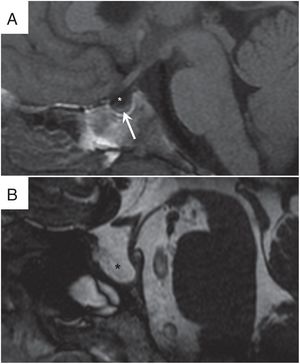

Pueden representar un signo adicional por imagen de la HII27. En el 11% de pacientes con HII se han identificado meningoceles en el cavum de Meckel o en el ápex petroso, y en un 9%, aumento del diámetro del cavum de Meckel (fig. 6)28. También se han descrito granulaciones aracnoideas intraóseas en el resto de la base de cráneo, predominantemente en las alas esfenoidales29. A través de las erosiones óseas y los defectos osteodurales pueden producirse fugas de LCR a oído medio o senos paranasales12.

Meningoceles y granulaciones aracnoideas en la base del cráneo. A) Secuencias STIR coronal y FIESTA (fast imaging employing steady-state) coronal en las que se identifica meningoceles del cavum de Meckel (asteriscos) y meningocele localizado en la zona medial del ala mayor derecha del esfenoides (puntas de flecha huecas). B) tomografía computarizada de peñascos, imagen transversal, donde se visualizan múltiples defectos óseos que afectan a la tabla interna de ambas alas esfenoidales correspondientes a granulaciones aracnoideas intraóseas (puntas de flecha negras).